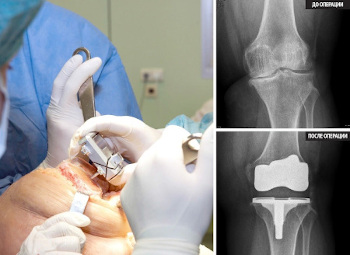

Zamjena zgloba je veoma skupa i veoma ozbiljna operacija.

Endoproteza koljenskog zgloba, fotografija.